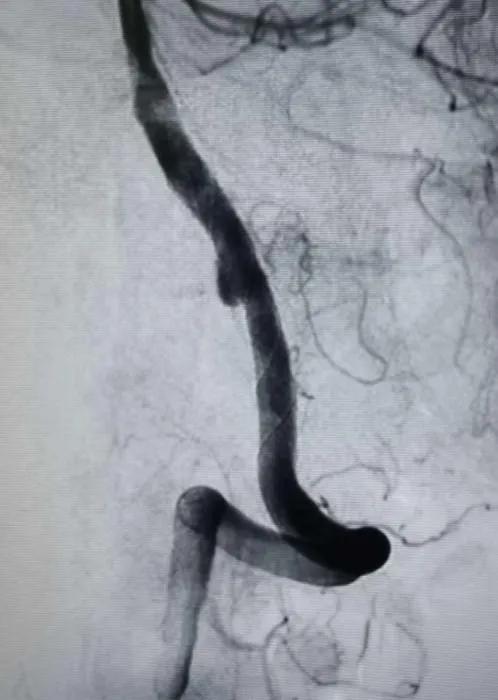

造影显示病变部位造影剂滞留。载瘤动脉通畅,脊髓前动脉通畅。后分别行左右颈内动脉及右侧椎动脉正侧位造影,未见明显血管异常。

结束手术,患者麻醉清醒后安全返回病房,无神经功能缺失。7天后,患者康复出院。限期随访。